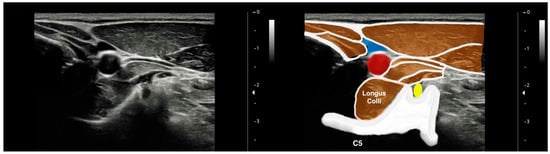

2.4.1. Cervical Multifidus and Longus Colli Imaging Acquisition